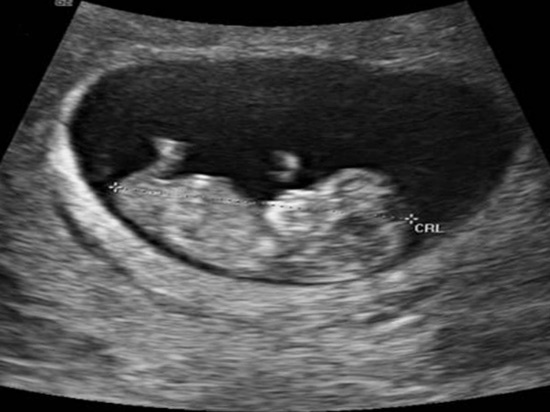

Imediat după obținerea unui test de sarcină pozitiv, este indicată programarea la medicul obstetrician. Prima vizita la medic are scopul de a stabili diagnosticul de sarcină, de a aprecia vârsta gestațională prin măsurarea ecografică a embrionului, precum și de a corela vârsta gestațională stabilită ecografic cu cea indicată de data ultimei menstruații. Tot cu ocazia primei vizite se vor lămuri o serie de întrebări legate de sarcină, de simptomele de prim trimestru, posibilele complicații care pot apărea, precum și principalele patologii care pot perturba evoluția normală ei normală. O sarcină sănătoasă presupune vizite regulate la medic.

În primul trimestru de sarcină sunt indicate următoarele examinări și teste: examen ecografic - care poate oferi informații despre localizarea sarcinii, evolutivitatea ei, precum și despre placentă; daca exista riscul unor anomalii genetice se vor indica o serie de teste genetice (probele fiind prelevate de la nivelul vilozităților corionice - de la nivelul placentei), care pot oferi rezultate mult mai rapid decât în cazul amniocentezei, care se poate efectua în al doilea trimestru de sarcină; există, de asemenea, și teste neinvazive pentru screeningul sindromului Down, folosind o combinație între măsurătorile ecografice (pliul nucal) și testele de sânge, sau mai recent apărute identificarea ADN-ului fetal în sângele matern (NIPT).